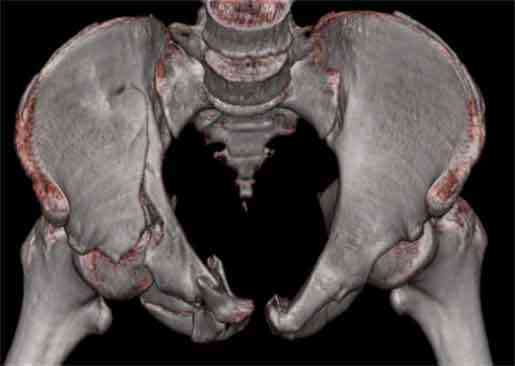

Не смог разглядеть на представленных картинках частичное повреждение левого КП, повреждение Денис1-2 справа? 3Д реконструкции в инлет и боковой проекциях убедительно не демонстрируют типа повреждения задних отделов тазового кольца(справа боковая масса скомпремирована), Наверное, у тебя есть возможность оценить тип перелома крестца по прямой проекции 3Д.

По поводу классификации повреждения тазового кольца( по тем данным . что видны на представленных картинках):

по Pennal et al.- латеральное компрессионное повреждение тип В(ротационно-нестабильное (внутренняя ротация), вертикально стабильное)

по Tile classif. тип В2-1 - частично стабильное повреждение с неполным разрывом задней дуги.

По вертлуге- смог разглядеть только изолированный перелом передней колонны.

Насколько я понял из твоего письма, обращенного к анонимному vit, ты не видишь показаний к реконструкции перелома. Я бы взялся за реконструкцию(илео-ингвинальный доступ), хоть прошел и месяц после травмы: боковая 3Д показывает смещение нагрузочной зоны впадины, что однозначно будет способствовать разрушению хряща головки и впадины( особенно у 16 летнего пациента с ожидаемым высоким уровнем активности) + изменение геометрии впадины за счет неустраненного смещения фрагментов колонны (КТ, 3Д данные).

На мой взгляд, без реконструкции этот сустав обречен (концепция вторичной конгруэтности в данных условиях работать не будет), реконструкция дает шанс на восстановление функции сустава.

В данном случае 3D и корональные срезы КТ менее информативны, чем поперечные. Согласен с левосторенним минимальным повреждением КПС, но не смог уловить перелом крестца.

По представленным материалам, мне кажется, перелом был передней колонны ацетабулум с минимальным вовлечением нагрузочной поверхности сустава, левосторенний повреждение КПС и лонных костей.